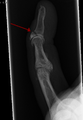

- X-ray showing fracture at the insertion of the extensor tendon

- A mallet finger without an associated fracture